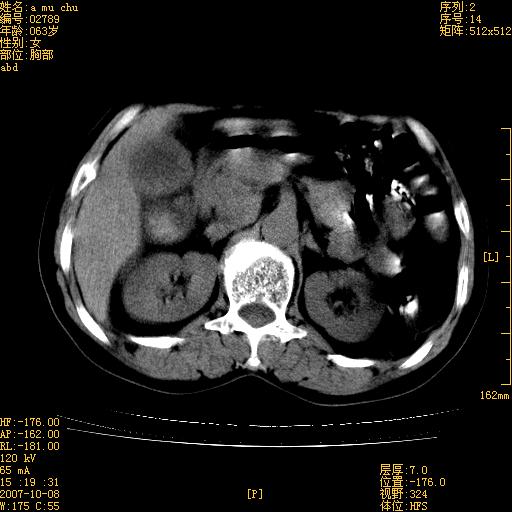

以下是引用王维浦在2007-10-17 21:02:00的发言:[br]胆囊增大,囊壁明显不规则增厚,邻近肝组织浸润,肝内外胆管无扩张。诊断:胆囊ca;[br]胰头软组织肿块影,考虑是由转移肿大的胰后淋巴结、没有肠道准备的十二指肠及胰头共同形成。[br]

以下是引用zhangzexing在2007-10-18 7:13:00的发言:[br]支持胰头占位,慢性胆囊炎. 2.肝左叶前外侧段占位,血管瘤?建议增强

以下是引用影像实习生在2007-10-17 19:49:00的发言:[br]支持胰头占位,慢性胆囊炎. 2.肝左叶前外侧段占位,血管瘤?建议增强.

以下是引用刘振江在2007-10-17 19:42:00的发言:[br]没有增强,胰头癌?胆囊及肝左叶占位?